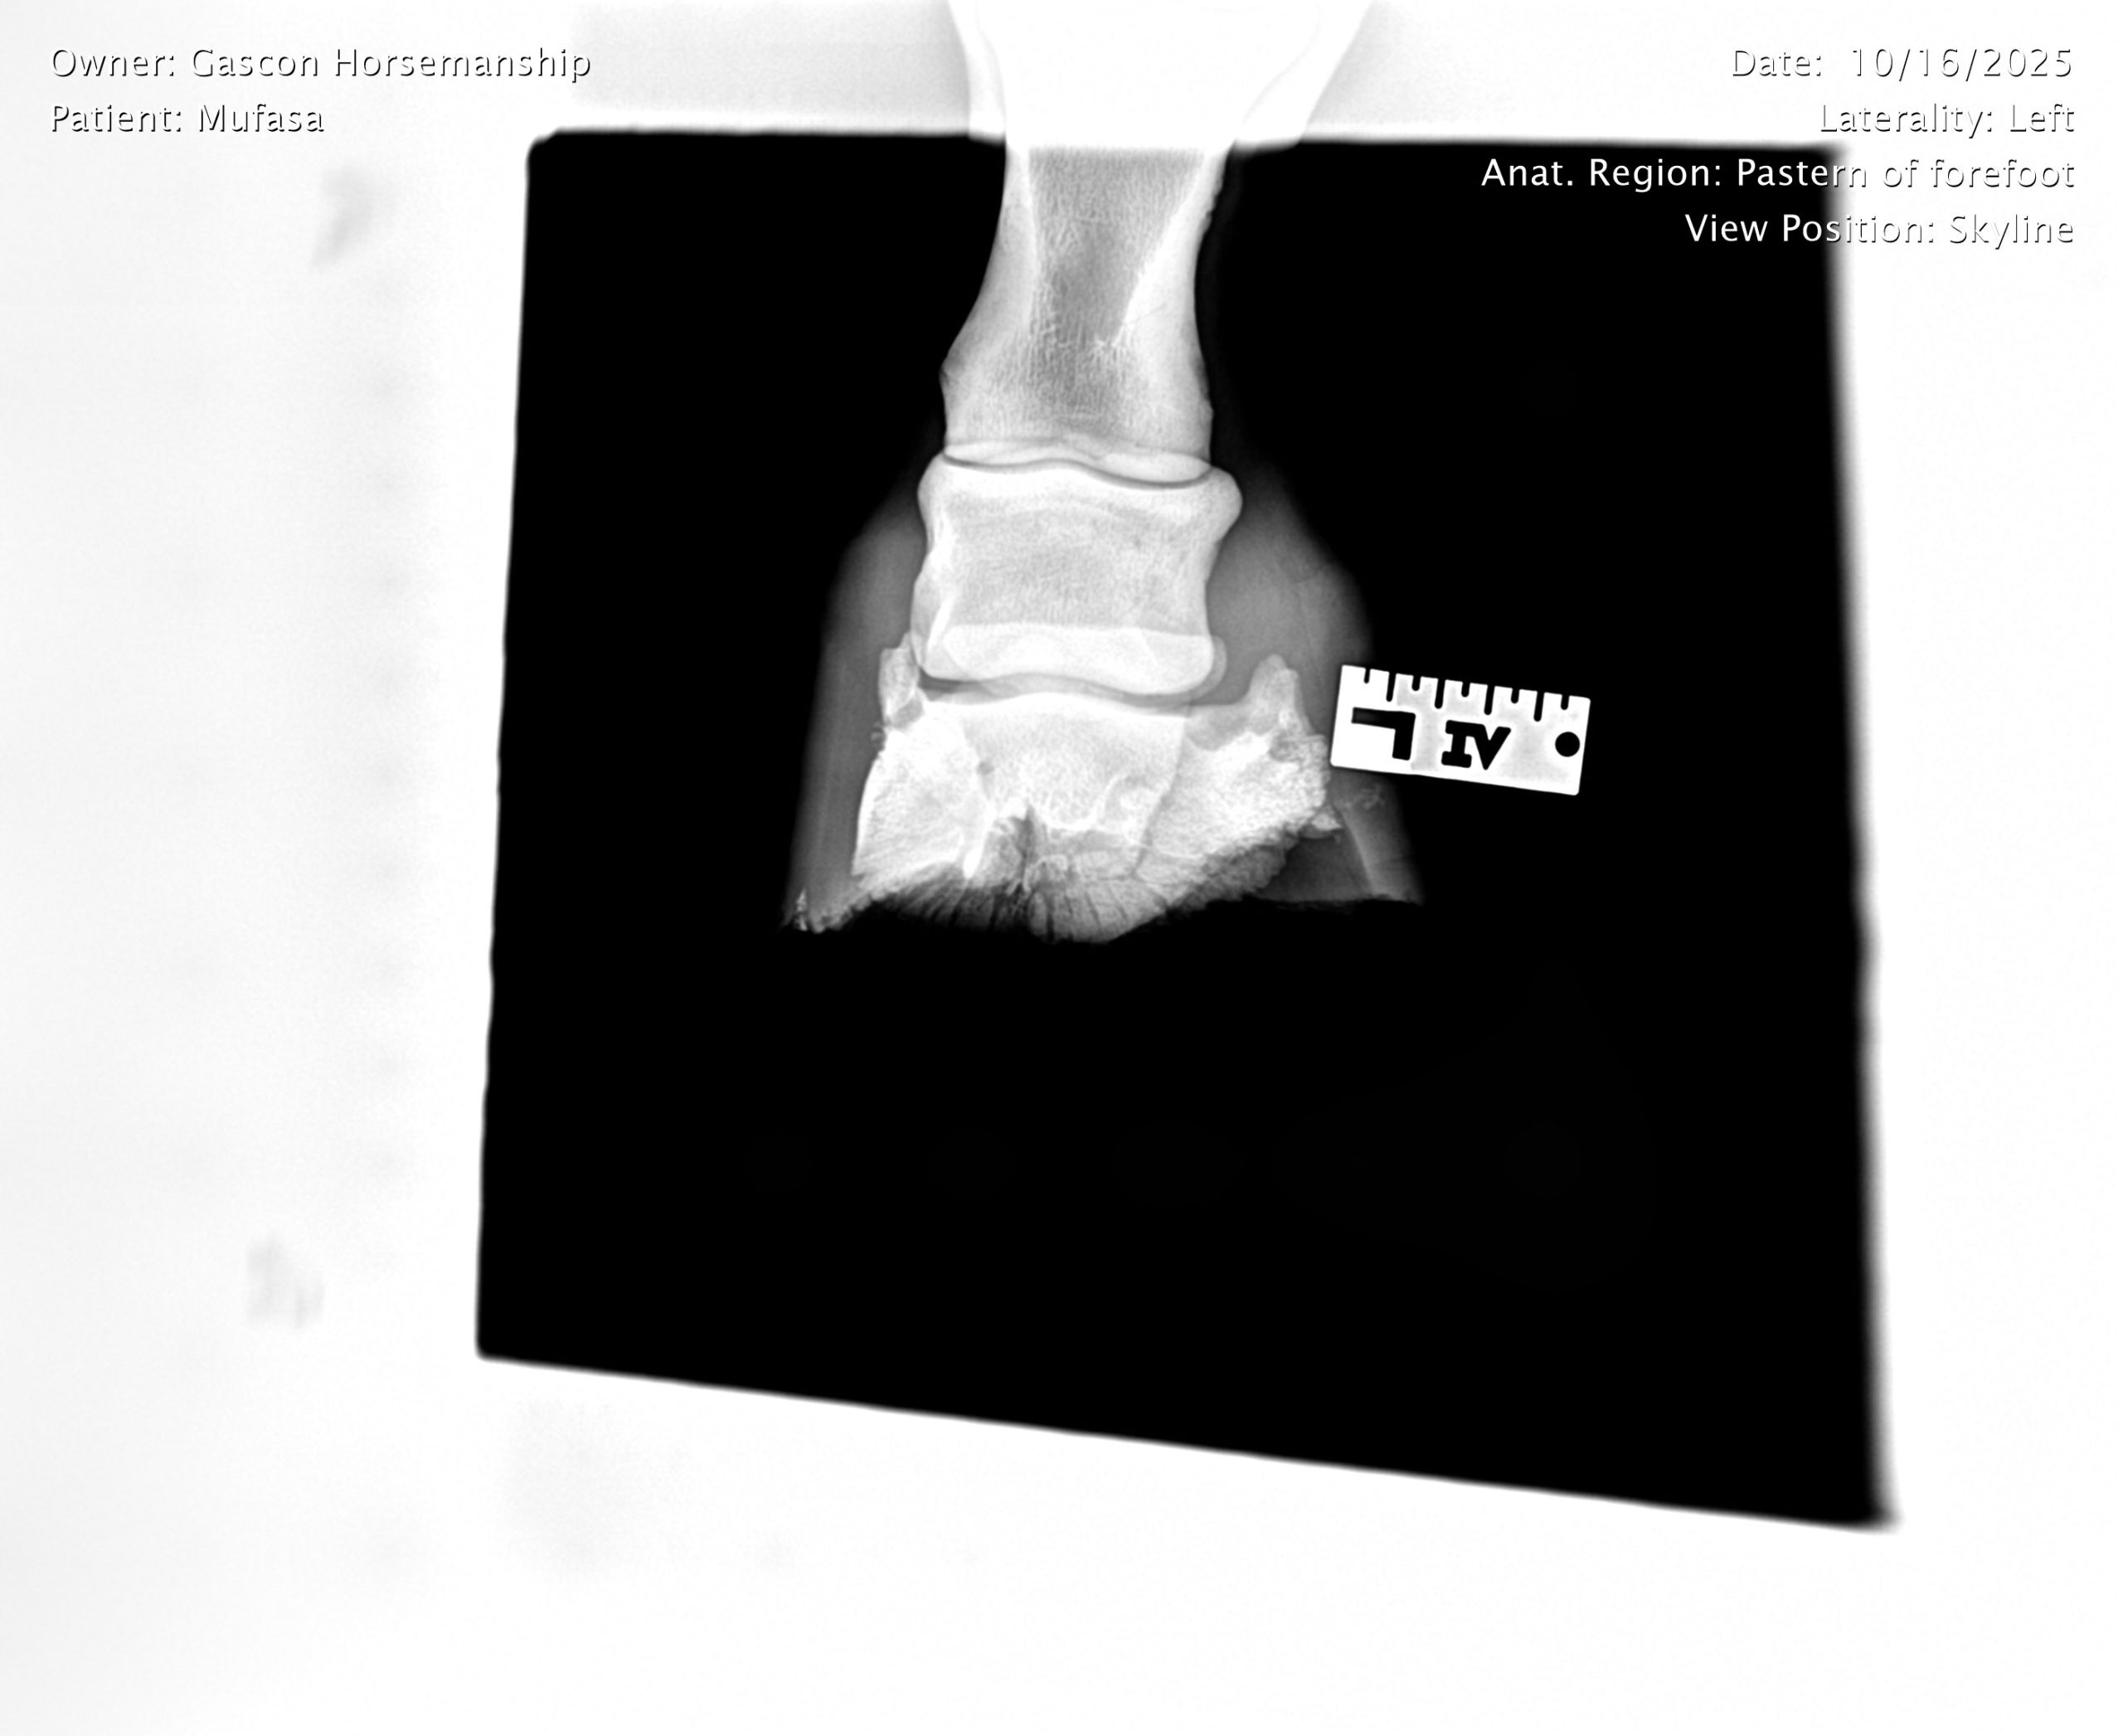

He already has a full pre-purchase exam on file, complete with 25 X-rays included in his album.